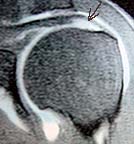

The wedge shaped light area indicated by the arrow is dye that had entered an void where there should be no void.

It turns out that I had completely torn in half the middle tendon (suprasinatus) of three large tendons that make up the rotator cuff, the structure that aids in lifting the arm. The reason I was still able to use the arm was that because tendons don't have nerves there wasn't any pain and the other two tendons compensated for the loss of the middle, and most important, tendon. Left uncorrected, the condition would be degenerative and in a few years I wouldn't be able to raise the arm and the damage would be so bad that it might not be repairable. I needed surgery and I needed it soon.